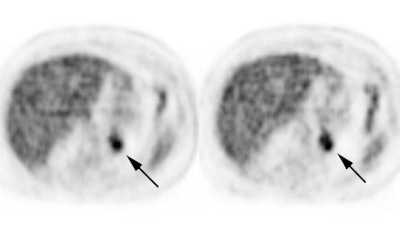

|

Benign adrenal lesion with FDG uptake: The patient shown below had a left adrenal mass which had remained stable for 2 years (white arrow). The stability over time and CT features would be consistent with a benign adrenal lesion- likely an adenoma. Note the marked FDG uptake within the mass on PET imaging (black arrows). Benign adrenal adenomas can accumulate FDG resulting in false positive exams. The use of PET/CT has been shown to improve the specificity of the PET exam. |